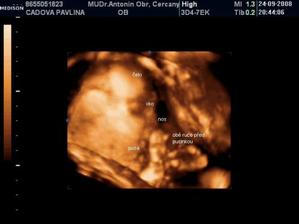

• 24.9.2008 – 4D ultrazvuk, potvrzena holčička